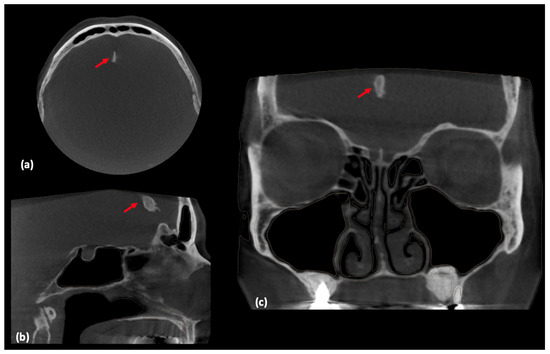

Artificial Intelligence-Assisted Segmentation of a Falx Cerebri Calcification on Cone-Beam Computed Tomography: A Case Report

2. Case Report and AI Application